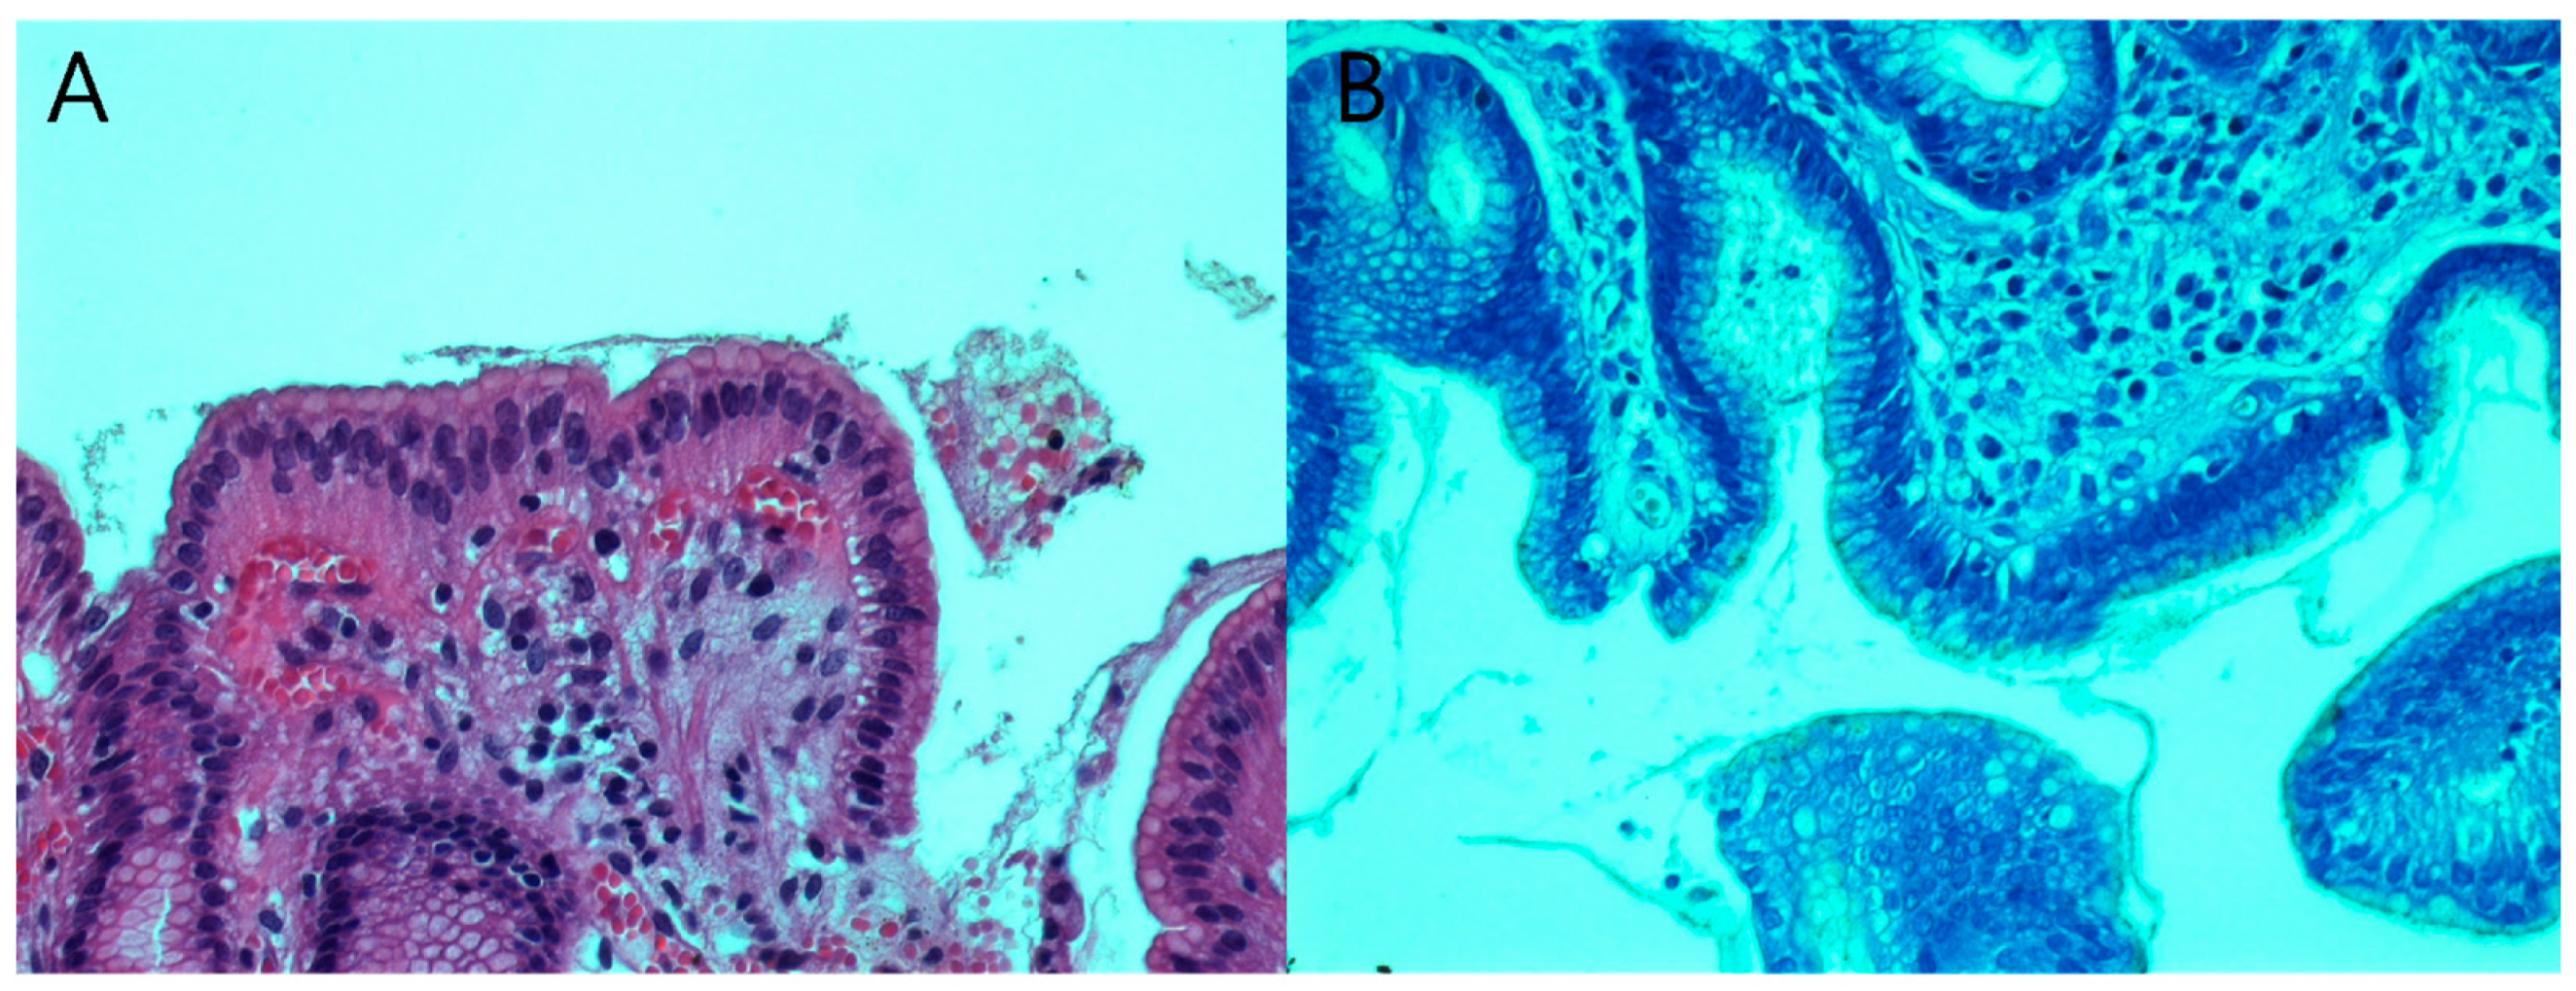

2.4. Histopathological Examination

- Fallone, C.A.; Loo, V.G.; Lough, J.; Barkun, A.N. Hematoxylin and Eosin Staining of Gastric Tissue for the Detection of Helicobacter pylori. Helicobacter 1997, 2, 32–35. [Google Scholar] [CrossRef] [PubMed]

- Alkhamiss, A.S. Evaluation of Better Staining Method among Hematoxylin and Eosin, Giemsa and Periodic Acid Schiff-Alcian Blue for the Detection of Helicobacter pylori in Gastric Biopsies. Malays. J. Med. Sci. 2020, 27, 53–61. [Google Scholar] [CrossRef] [PubMed]